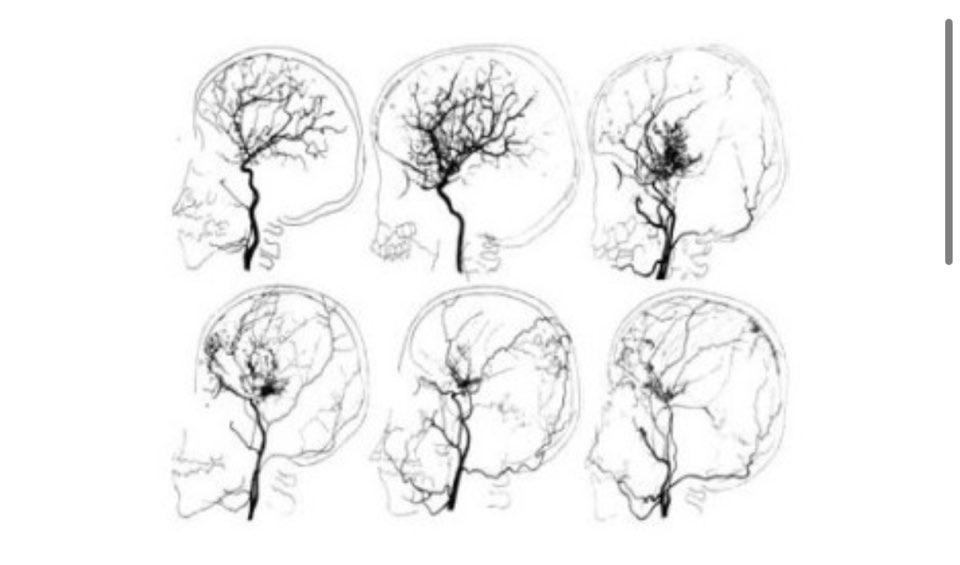

모야모야병은 대뇌에 혈류를 공급하는 데 중요한 역할을 하는 혈관과 모야모야 혈관이라는 작은 이상혈관이 내동맥 끝에서 좁아지는 질환으로 특별한 원인 없이 발생하는 것으로 알려져 있습니다.

일본 스즈키가 뇌혈관 동맥 조영상에서 '담배 연기가 피어오르는 모습'을 뜻하는 '모야모야'라는 이름이 붙었습니다.

모야모야병은 증상 의심이 가장 중요하며 CT, MRI, MRA, 뇌혈관조영술 등 영상진단이 필수입니다.

모야모야병은 주로 양쪽 혈관에 많이 발생하기 때문에 1차 수술 후 3개월 이상 경과 관찰 후 뇌와 뇌혈관 기능을 확인하고 반대편에서 2차 수술을 시행합니다.